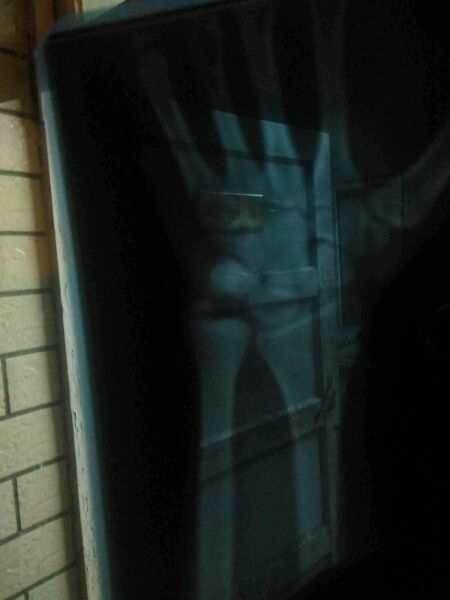

求助帖 帮看看是什么问题怎么治

骨折吧

截骨